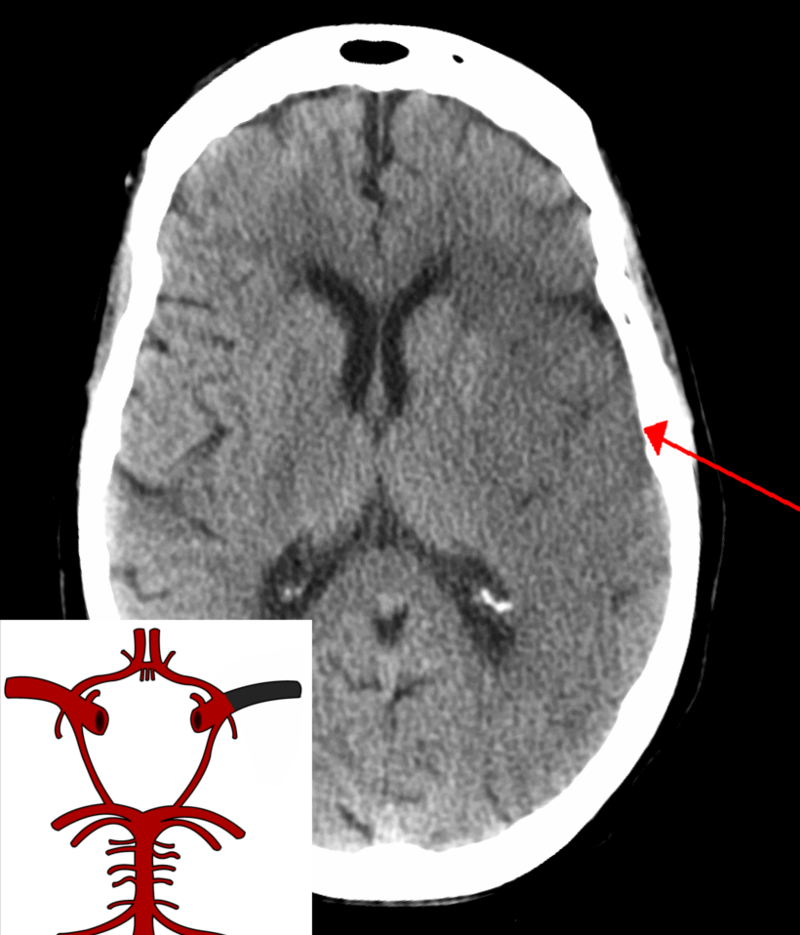

Ischemic Stroke

An ischemic stroke can cause regional ischemia that causes focal neurologic impairments that continue longer than 24 hours.

Transient ischemic attack (TIA) is the name given to an incident if the symptoms last less than 24 hours.

Subtypes of ischemic strokes include:

- Thrombotic (e.g. atherosclerotic plaque rupture)

- Embolic (e.g. from thromboemboli from the heart in atrial fibrillation)

- Lacunar (e.g. from hyaline arteriolosclerosis, an adverse effect of hypertension)

Symptoms of ischemic stroke depend on the region of brain involvement.

- A pure motor stroke results from the interior capsule being involved

- Thalamus causes a pure sensory stroke